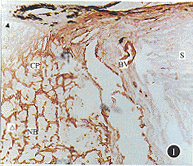

1.人Ⅳ型胶原蛋白免疫过氧化酶染色:正常视乳头筛板存在大量Ⅳ型胶原蛋白(图1,2)。纵切标本显示Ⅳ型胶原蛋白在筛板区呈板状、横向分布构成筛板的主体。横切面观察,IV型胶原蛋白形成一完好连续薄膜包绕筛板,高倍镜下观察在筛板核心存在细丝样阳性染色。神经束中无阳性染色。在视乳头筛板前区,只有血管处有阳性染色。在筛板后区,阳性染色物衬覆神经束,血管壁也存在阳性染色。视乳头中血管内皮基底膜作为Ⅳ型胶原蛋白阳性对照。巩膜部除血管外,无Ⅳ型胶原蛋白着染。

图1 正常成人视乳头Ⅳ型胶原蛋白免疫过氧化酶染色,▲筛板前区,CP筛板,△筛板后区,S巩膜,BV血管,NB神经膜 纵切观察 ×6